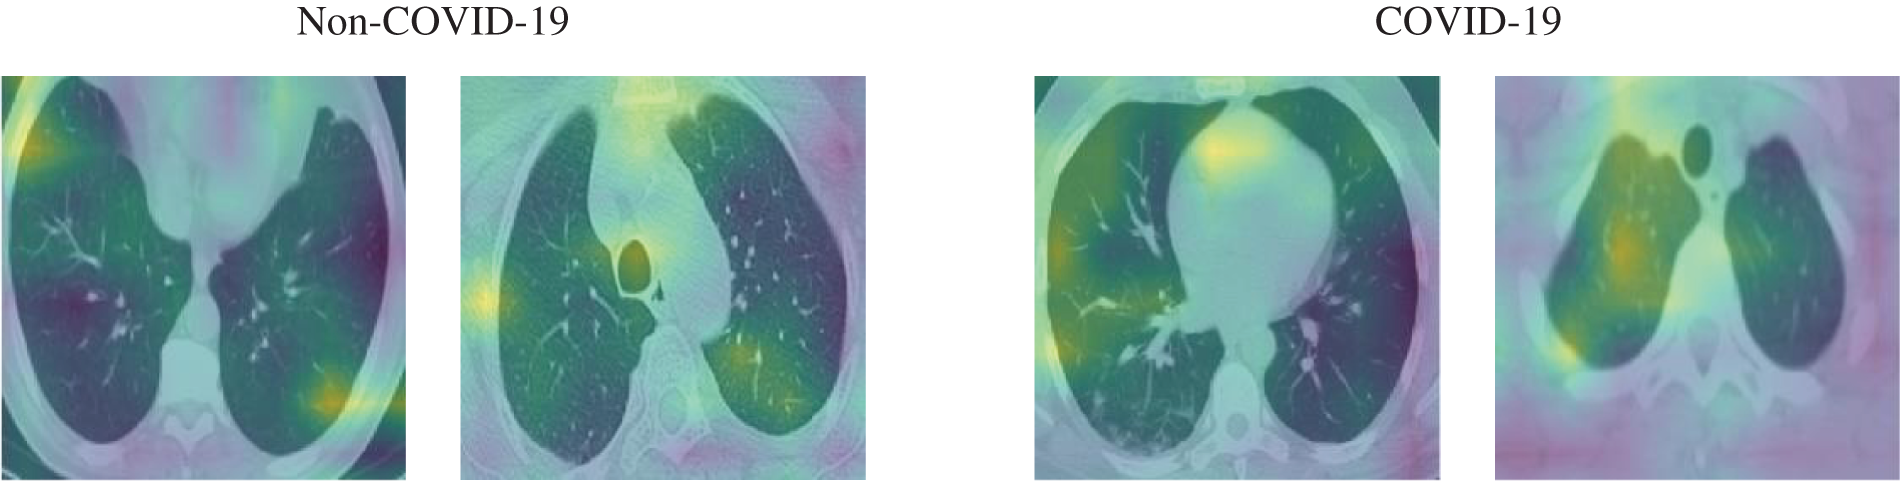

In this section, the results of the experiments are presented and discussed to evaluate the proposed system. We reported the results based on the aforementioned performance metrics. First, we presented an example from the input CT scan image through the different stages of the system, i.e., generation of perturbation and adversarial example, as presented in Fig. 7, and some of the activation maps, as presented in Fig. 8.

Figure 8: Samples of the activation maps of both COVID-19 and non-COVID-19